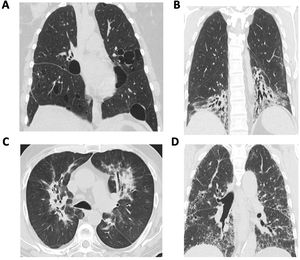

Overview of diagnosis of autoimmune-associated ILDThe diagnostic evaluation of patients with autoimmune-associated ILD requires multi-disciplinary collaboration and a coordinated approached to decision making. A multi-disciplinary meeting (MDM) involving pulmonologists, rheumatologists, radiologists, and pathologists represents the gold standard for ILD diagnosis.4–6 The MDM provides a forum to discuss individual patient cases and review relevant clinical, radiological, laboratory and pathological findings. Because different radiological and histopathological patterns of ILD occur in patients with autoimmune rheumatic diseases (Fig. 1), expert input from radiologists and pathologists may help resolve diagnostic dilemmas. Additional members of an ILD–MDM may include psychologists, social workers, respiratory therapists, transplant specialists, thoracic surgeons, interventional pulmonologists, and palliative care providers. Studies have demonstrated improved diagnostic confidence and interobserver agreement after MDM compared with the individual components of an MDD (e.g., pathology, radiology).7–9 For the diagnosis of autoimmune-associated ILD, rheumatologists play an important role in guiding diagnostic decision making.10,11 For example, one study reported that approximately 10% of patients received a new diagnosis of an autoimmune-associated ILD after undergoing a MDM.7 In another study, rheumatology assessment reclassified 21% of patients with IPF as CTD-ILD.12